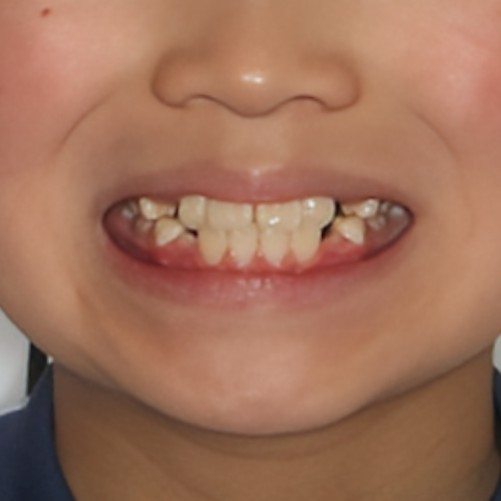

第1期治療開始時

顔貌写真

口腔内写真

年齢

9歳 男性

主訴(患者様のお悩み)

歯のデコボコを治したい